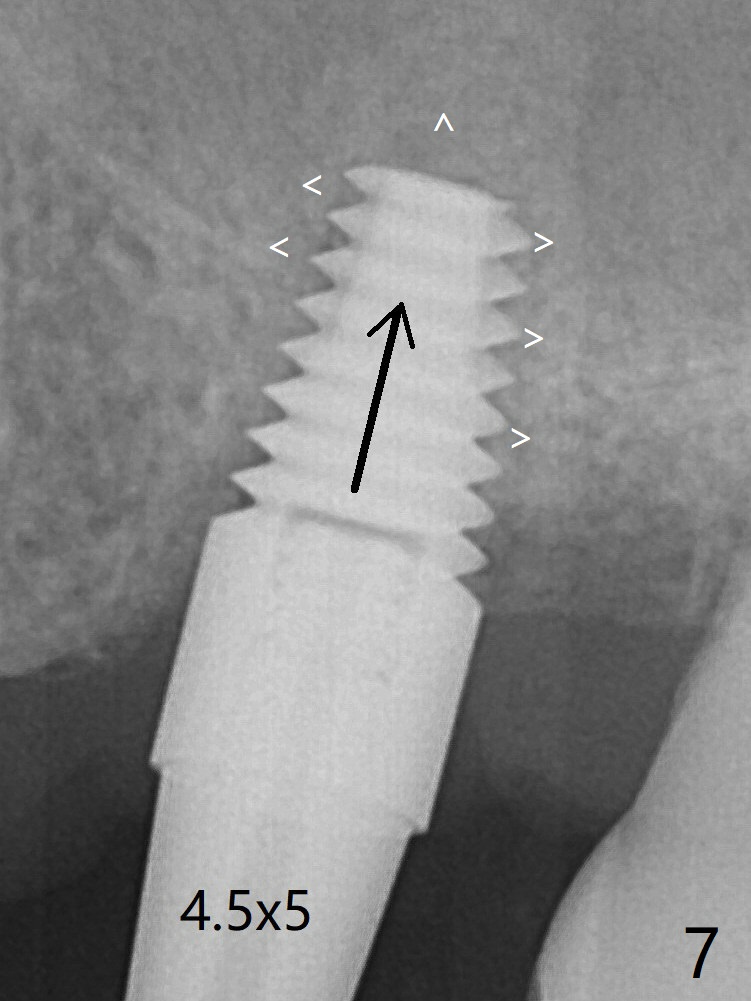

Depth of osteotomy is controlled with IS drill stoppers. After sequential osteotomy free hand, a 5x11 mm Tatum tapered tap is used to break through the sinus floor (Fig.5) and later sinus lift is conducted with the tap, a 5x11 mm implant and Vanilla allograft (Fig.6 *). When the implant is placed deeper (Fig.7 arrow), more bone condensation and sinus lift occur (arrowheads). Allograft is packed in the remaining socket gaps (Fig.9 *). The bone in sinus lift is mature 5 months postop (Fig.12,13). The first 1-2 implant threads are expected to be filled with mature bone in the near future (*). Since the abutment seems long enough for retention, temp bond is used for cementation (Fig.14). Water pik is being applied.